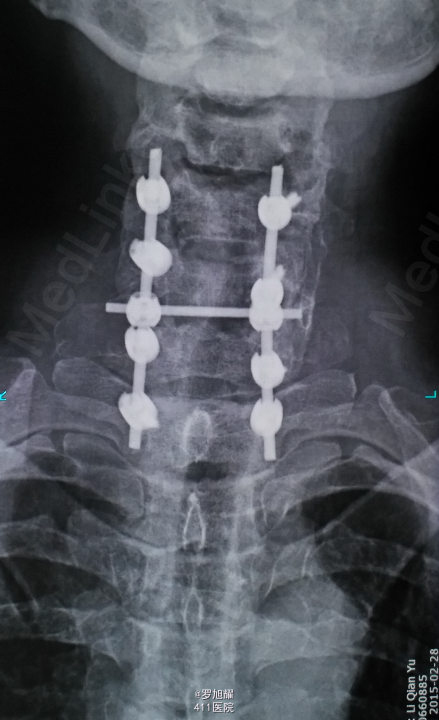

查体:双上肢前臂及以远感觉丧失,躯体自第二肋间平面以下感觉丧失。耸肩可,双侧三角肌、肱二三头肌肌力2级,腕关节屈伸、旋转及各指肌力0级。腱反射阴性,但球海绵体反射已经阳性。影像学检查示颈椎骨折脱位伴颈髓损伤。

诊断:颈6/7骨折脱位伴高位截瘫。处理:立即甲强龙冲击、脱水、保胃、营养神经治疗。首选治疗方案是颅骨牵引复位后前路融合固定,较后路稳定,出血也少,和家属谈话后开始颅骨牵引复位,4kg起步,每半小时增加1kg直至14kg,调整颈椎屈伸位,再加用手法牵引仍不能复位。改用备选方案,急诊行后路切开减压撬拨复位内固定,术后瘫痪症状部分改善。随访3月双上肢前臂及手部感觉恢复,仅双手掌尺侧及小指感觉障碍,双侧三角肌、肱二三头肌肌力4-5级,腕关节屈伸、旋转肌力左侧3级,右侧3-4级,但各指肌力仍0级。